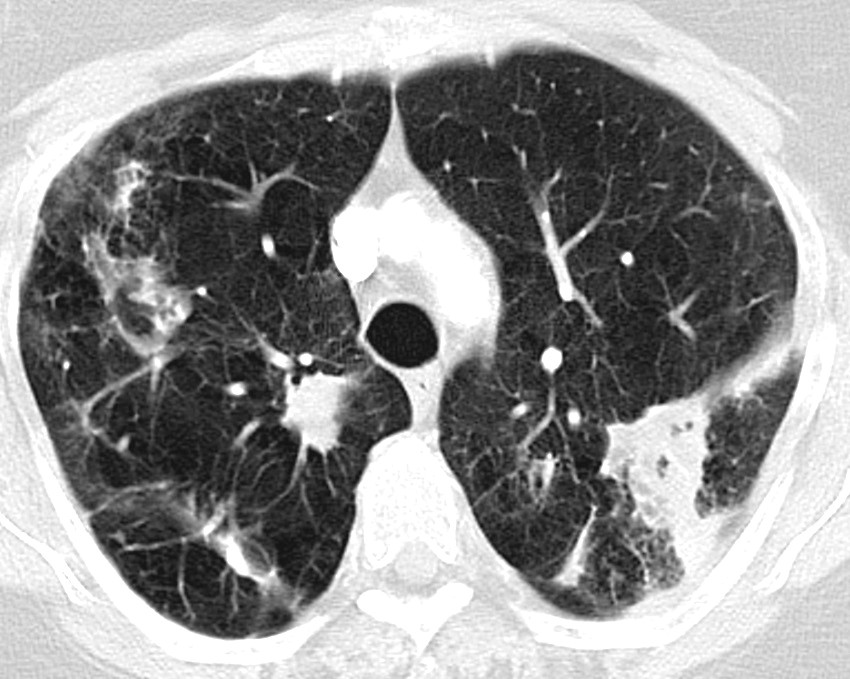

Ved mistanke om lungesykdom som skyldes ikke-tuberkuløse mykobakterier bør pasienten utredes med CT thorax. De to vanligste radiologiske presentasjonsformene er fibrokavitær og nodulær bronkiektatisk form (23, 24). Den fibrokavitære formen har kavitære lesjoner, hyppigst i overlappene, med radiologiske funn som ligner tuberkulose (figur 1). Denne formen har ofte et mer aggressivt forløp og ses hyppigst hos eldre menn som røyker eller har annen lungesykdom, f.eks. kronisk obstruktiv lungesykdom eller gjennomgått tuberkulose. Nodulær bronkiektatisk form preges av multifokale bronkiektasier og små noduli, oftest hos ikke-røykende, eldre kvinner. Denne formen er ellers overrepresentert blant pasienter med lav kroppsmasseindeks, skoliose, pectus excavatum, mitralprolaps og hos høye personer (17, 19).